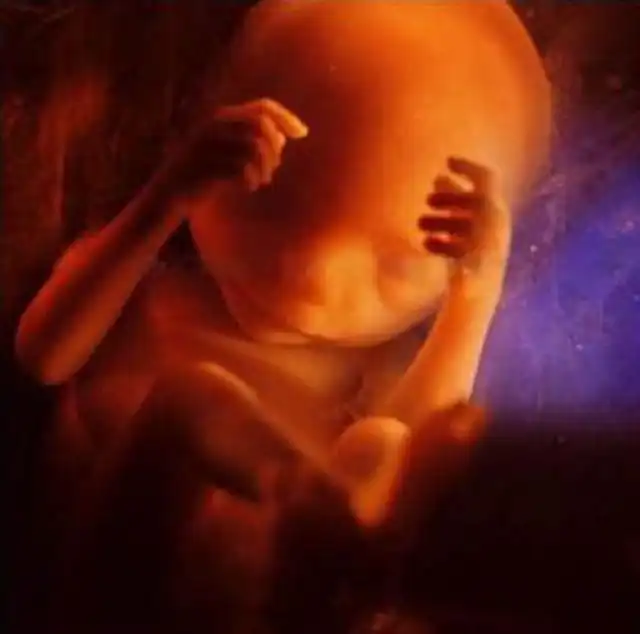

18 недель. Около 14 см. Зародыш теперь может воспринимать звуки из внешнего мира.

19 недель..

20 недель. Около 20 см. На голове уже начинают появляться волосы.